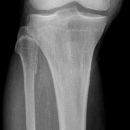

Kniegelenk

Unterschenkel

Knie